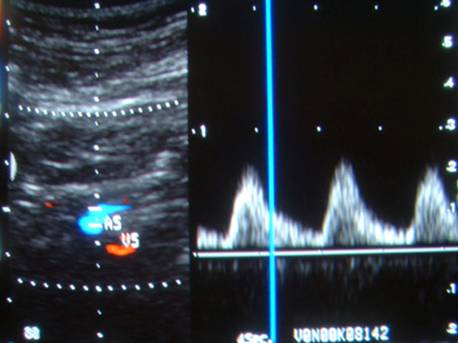

Slika 6. Prikaz vertebralne arterije i vene

Kao i kod karotidnih arterija određujemo dijametar vertebralne arterije (oko 4 mm), utvrđujemo postojanje depozita, obeležavamo smer kretanja krvi (stenoza ili okluzija istostrane potključne arterije dovodi do sindroma krađe krvi iz vert. art. i reverznog protoka krvi kroz ispitivanu vert. art.), merimo brzinu protoka krvi (vršna sistolna brzina ne sme biti manja od l0 cm /sec).